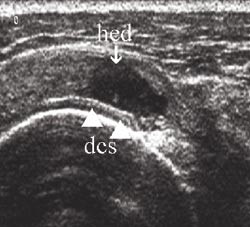

Rotatorcuffrupturer klassifiseres med ultralyd ut fra lokalisasjon, størrelse og grad (partiell, full tykkelse). Hovedlokalisasjonen er distalt i supraspinatussenen ved festet mot tuberculum majus (1). Det er beskrevet tre hoved- og tre tilleggskriterier for ultralydfunn ved cuffrupturer (3, 5). Hovedkriteriene har størst betydning og det kreves påvisning av minst ett av hovedkriteriene i to plan for ultralyddiagnosen rotatorcuffruptur. Sammen med et hovedkriterium støtter hvert av tilleggskriteriene sannsynligheten for diagnosen. Hovedkriteriene er hypoekkoisk defekt (fig 7), tap av konveksitet (fig 8 a, b) og skallet humerushode (fig 9a, b). Hypoekkoisk defekt er typisk for akutte rupturer og representerer en væskeansamling i defekten mellom rupturkantene (1). Tap av konveksitet og skallet humerushode er stadier i en progredierende degenerativ prosess med gradvis skade og retraksjon av rupturendene og herniering av bursavev og deltoidmuskel i defekten.

De tre tilleggskriteriene er den markerte fremstillingen av brusklaget i bunnen av cuffdefekten (double cortex sign) (fig 7), overflateforandringer på tuberculum majus (fig 8b) og væskeansamling i leddet og/eller bursa (fig 10a, b). Forandringene på tuberculum majus er følge av en mikrotraumatisering mellom den nakne beinoverflaten og acromion. Væskeansamling i leddet er best synlig i seneskjeden rundt det lange bicepshodet som hypoekkoisk halo, eller ved utposning av bakre leddkapsel (2, 6). Hollister og medarbeidere (7) fant en positiv prediktiv verdi for rotatorcuffruptur på 60 % ved væske i leddet, 70 % ved væske i bursa og 95 % ved væske begge steder, verifisert ved operasjon.

Figurene 2b, 3b, 4c, 5b, 6b, 8a og b er tatt med et Siemens Sonoline Antares ultralydapparat med 11,4 MHz lydhode, figurene 2b og 5b i tillegg med teknikk for utvidet bildefelt (extended field of view). Resten av ultralydbildene er tatt med et Siemens Sonoline Sienna ultralydapparat med 7,5 MHz lydhode. Figurene 1a, 1b, 2a, 3a, 4b, 5a og 6a er gjengitt med tillatelse fra Primal Pictures Ltd (). e-fig 3, e-fig 6, e-fig 11, e-fig 12 og e-fig 13 finnes i artikkelen på www.tidsskriftet.no